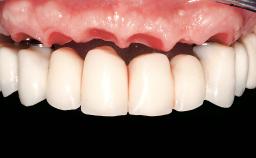

Immediate Loading of Eight Implants in the Maxilla and Six Implants in the Mandible and Final Restoration with Three-Unit and Four-Unit FDPs

Prosthesis Type FDP

Defining Characteristics Fully edentulous upper jaw to be rehabilitated with an implant-borne fixed dental prosthesis

Loading Protocol Immediate

Esthetic Risk High

Occlusal Scheme/Issues Anterior guidance